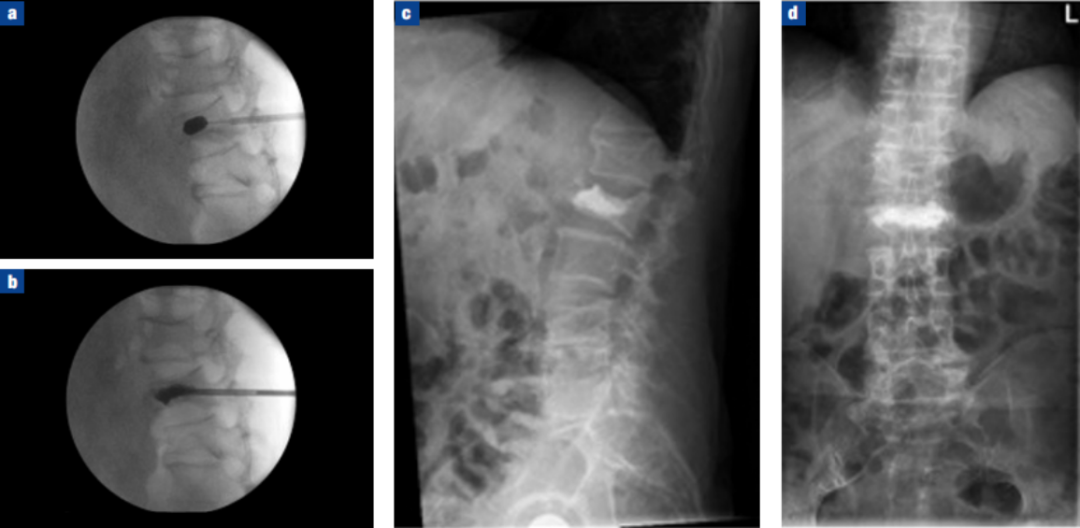

经皮球囊扩张椎体后凸成形术(PKP)

①正位、侧位影像监测下,经皮由椎弓根置入;

②置入导管球囊扩张,向气囊内充气扩张,以恢复椎体高度;

③放出气囊内气体,移走气囊,注入骨水泥维持矫正后形态

经皮球囊扩张椎体后凸成形术(PKP)病例